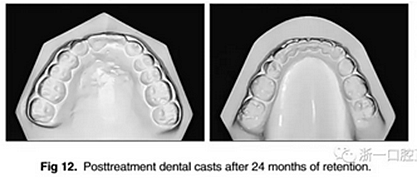

治療持續(xù)3年,患者始終保持積極和合作。口腔衛(wèi)生很好?;颊吆退母改付紝Y(jié)果感到滿意。經(jīng)過24個月的保持后,咬合保持得很好(圖11 ; 圖12)。在上牙弓中,應(yīng)用固定舌側(cè)保持器以防止任何復(fù)發(fā)傾向。在下牙弓中,治療后拔除第三磨牙。